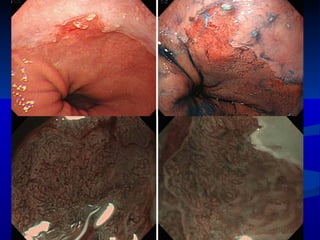

Narrow Band Imaging ( NBI)

NBI

Microscopia Confocal

Imagen con metapasia columnar endoscopica y metaplasia intestinal de AP